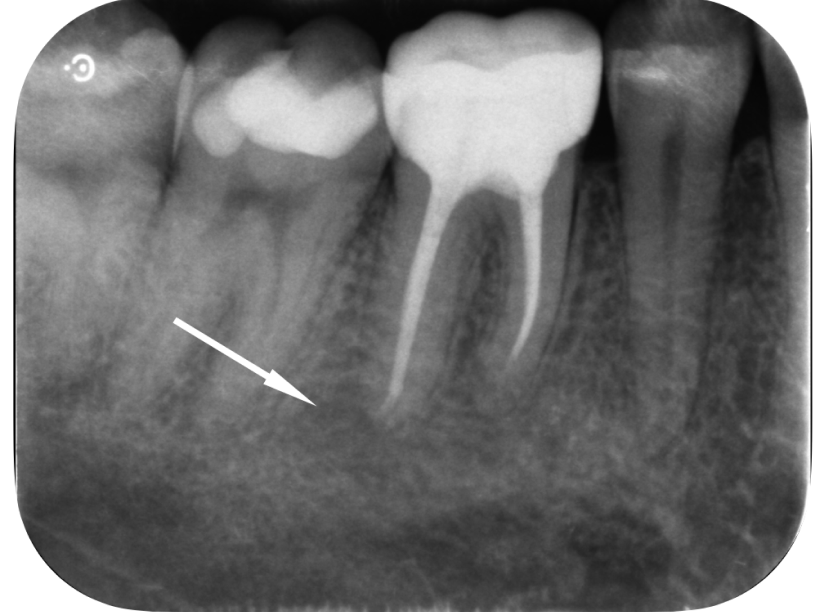

大臼歯の再根管治療を行った症例

タップで写真の拡大ができます。

Before&After(根管治療)

Before

主訴

歯茎が腫れて、噛むと違和感がある

治療内容

再根管治療(大臼歯)

治療期間

1ヶ月

治療費用

165,000

治療の

リスク

処置中に歯肉縁下におよぶ重度のう蝕や破折を認めた場合、治療を中断する可能性があります。術後も症状が残る場合は追加の処置が必要になる可能性があります。